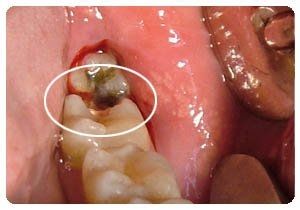

3、补牙法:补牙是针对已经蛀牙的孩子,牙齿上产生龋洞,就需要及时填补。>>点击在线咨询详情<<

牙博士口腔引进的纳米树脂补牙(咨询技术细节)采用的是当代科技生产的补牙材料,其填料的颗粒度达到纳米级。树脂材料具有半透明性,且具有乳光色泽,与材料的半透明性一起,可以满足更多补牙者的需求其性能较过去的复合树脂类材料有较大提高,色泽好、耐磨、不易脱落,是补牙时很好的选择!>>点击在线咨询详情<<

蛀牙的形成是一个循序渐进的过程,如果发现孩子已患有蛀牙,尽可能的在早期去寻求治疗,这样牙齿修复快,疼痛少,也不会面临拔牙的危害>>点击在线咨询详情<<